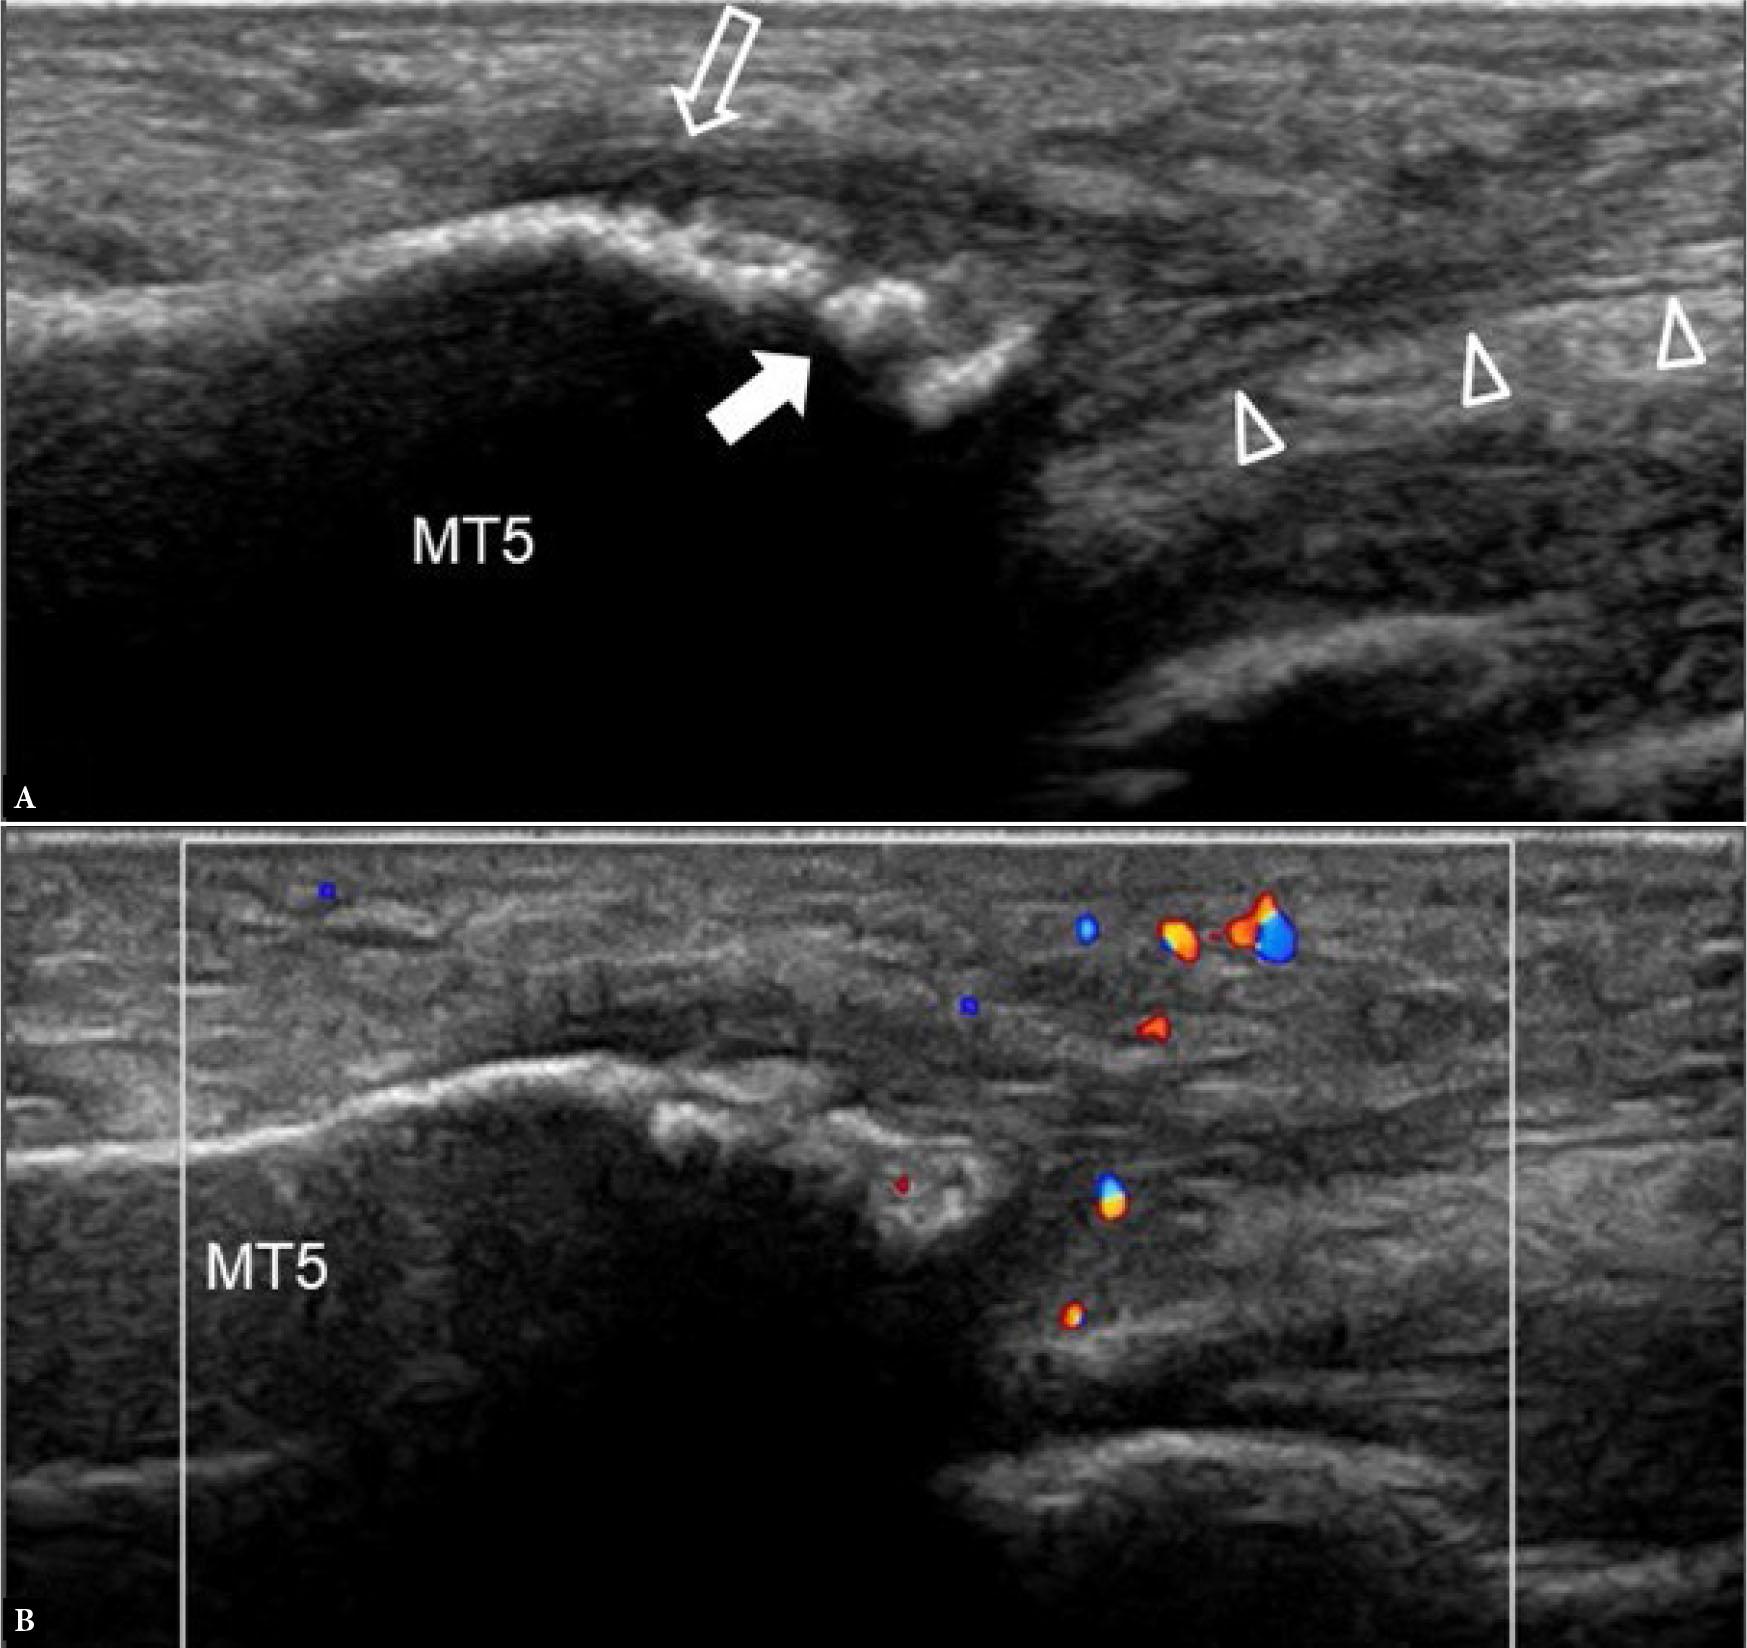

Enthesitis

Tendinous, ligamentous, or fascial insertion into bone can show thickening and hyperemia secondary to mechanical overloading or a systemic disease (e.g. spondyloarthritis, such as psoriatic arthritis). More common examples are the peroneus brevis tendon insertion and lateral band plantar fascial insertion to the 5th metatarsal base (Fig. 31) as well as the posterior tibialis tendon insertion into the medial pole of the navicular bone. When evaluating such structures, the examiner should use minimal transducer pressure during color Doppler assessment to optimize the detection of tissue hyperemia (Fig. 28, Fig. 31).

Fig. 31.

57-year-old female with unilateral lateral foot pain for several months. (A) Longitudinal greyscale US image shows moderate cortical hyperostosis (arrow) of the 5th metatarsal (MT5) base at the insertion of the lateral band plantar fascia (arrowheads). The more lateral insertion of peroneus brevis tendon (open arrow) is also shown. (B) Longitudinal color Doppler US image shows moderate localized hyperemia. Appearances are compatible with enthesitis as a feature of peripheral spondyloarthropathy. Subsequent MRI revealed inflammatory sacroiliitis due to ankylosing spondylitis